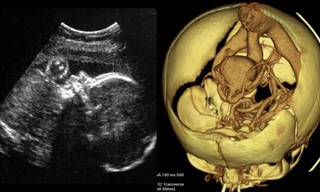

TP - Sau khi đào các khu mộ cổ ở vùng Andean, miền nam của tỉnh Andahuaylas tại Peru, các nhà khảo cổ học của Đại học California đã tìm được 32 thi hài của những người Peru cổ sống cách đây gần 1000 năm.